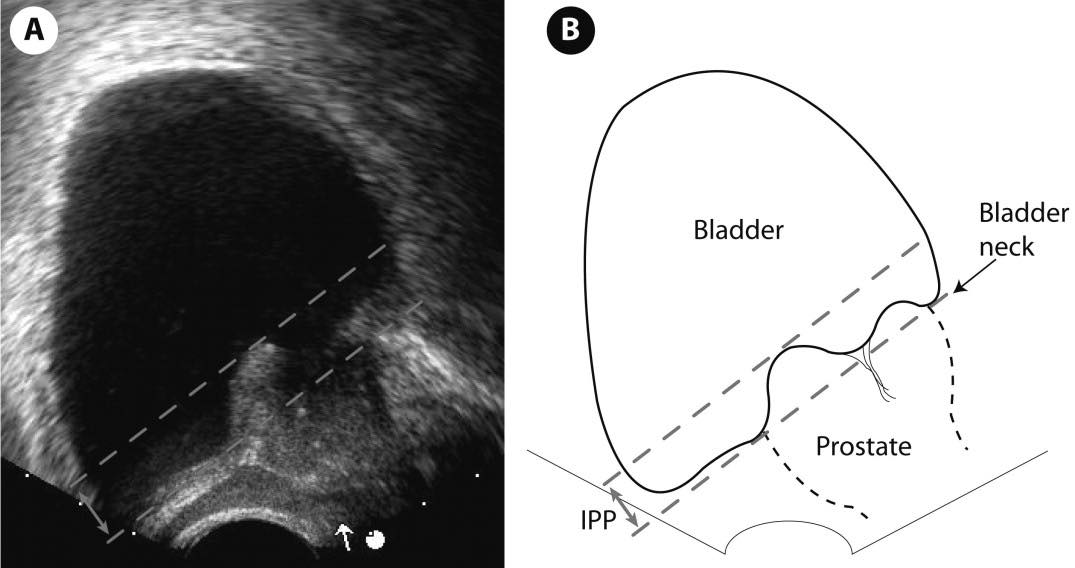

Hình ảnh này cho thấy các mức độ phì đại tuyến tiền liệt (BPH) trên siêu âm dựa trên thể tích tuyến tiền liệt và tình trạng lồi tuyến tiền liệt vào bàng quang (IPP):

Vì vậy, mức độ nghiêm trọng được xác định bởi cả thể tích tuyến tiền liệt và mức độ lồi vào bàng quang (IPP).